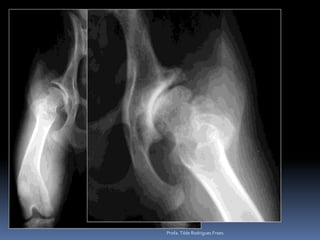

Animal: Mike, canino Canino, macho, 11 anos, ROTTHX: Claudicação posteriores    Déficit de propriocepçãoProfa. Tilde Rodrigues Froes

Animal: Mike, caninoCanino, macho, 11 anos, ROTTHX: Claudicação posteriores Déficit de propriocepçãoProfa. Tilde Rodrigues Froes